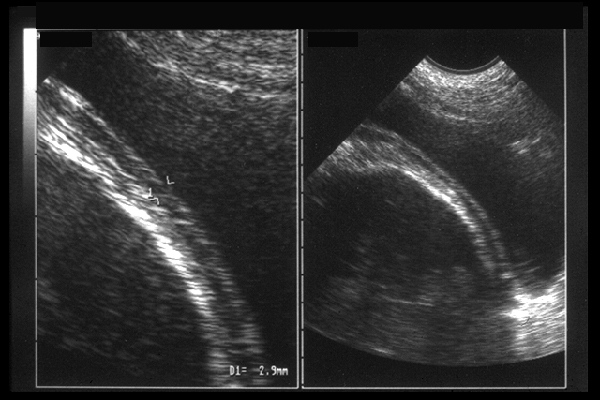

Amincissement du segment inférieur